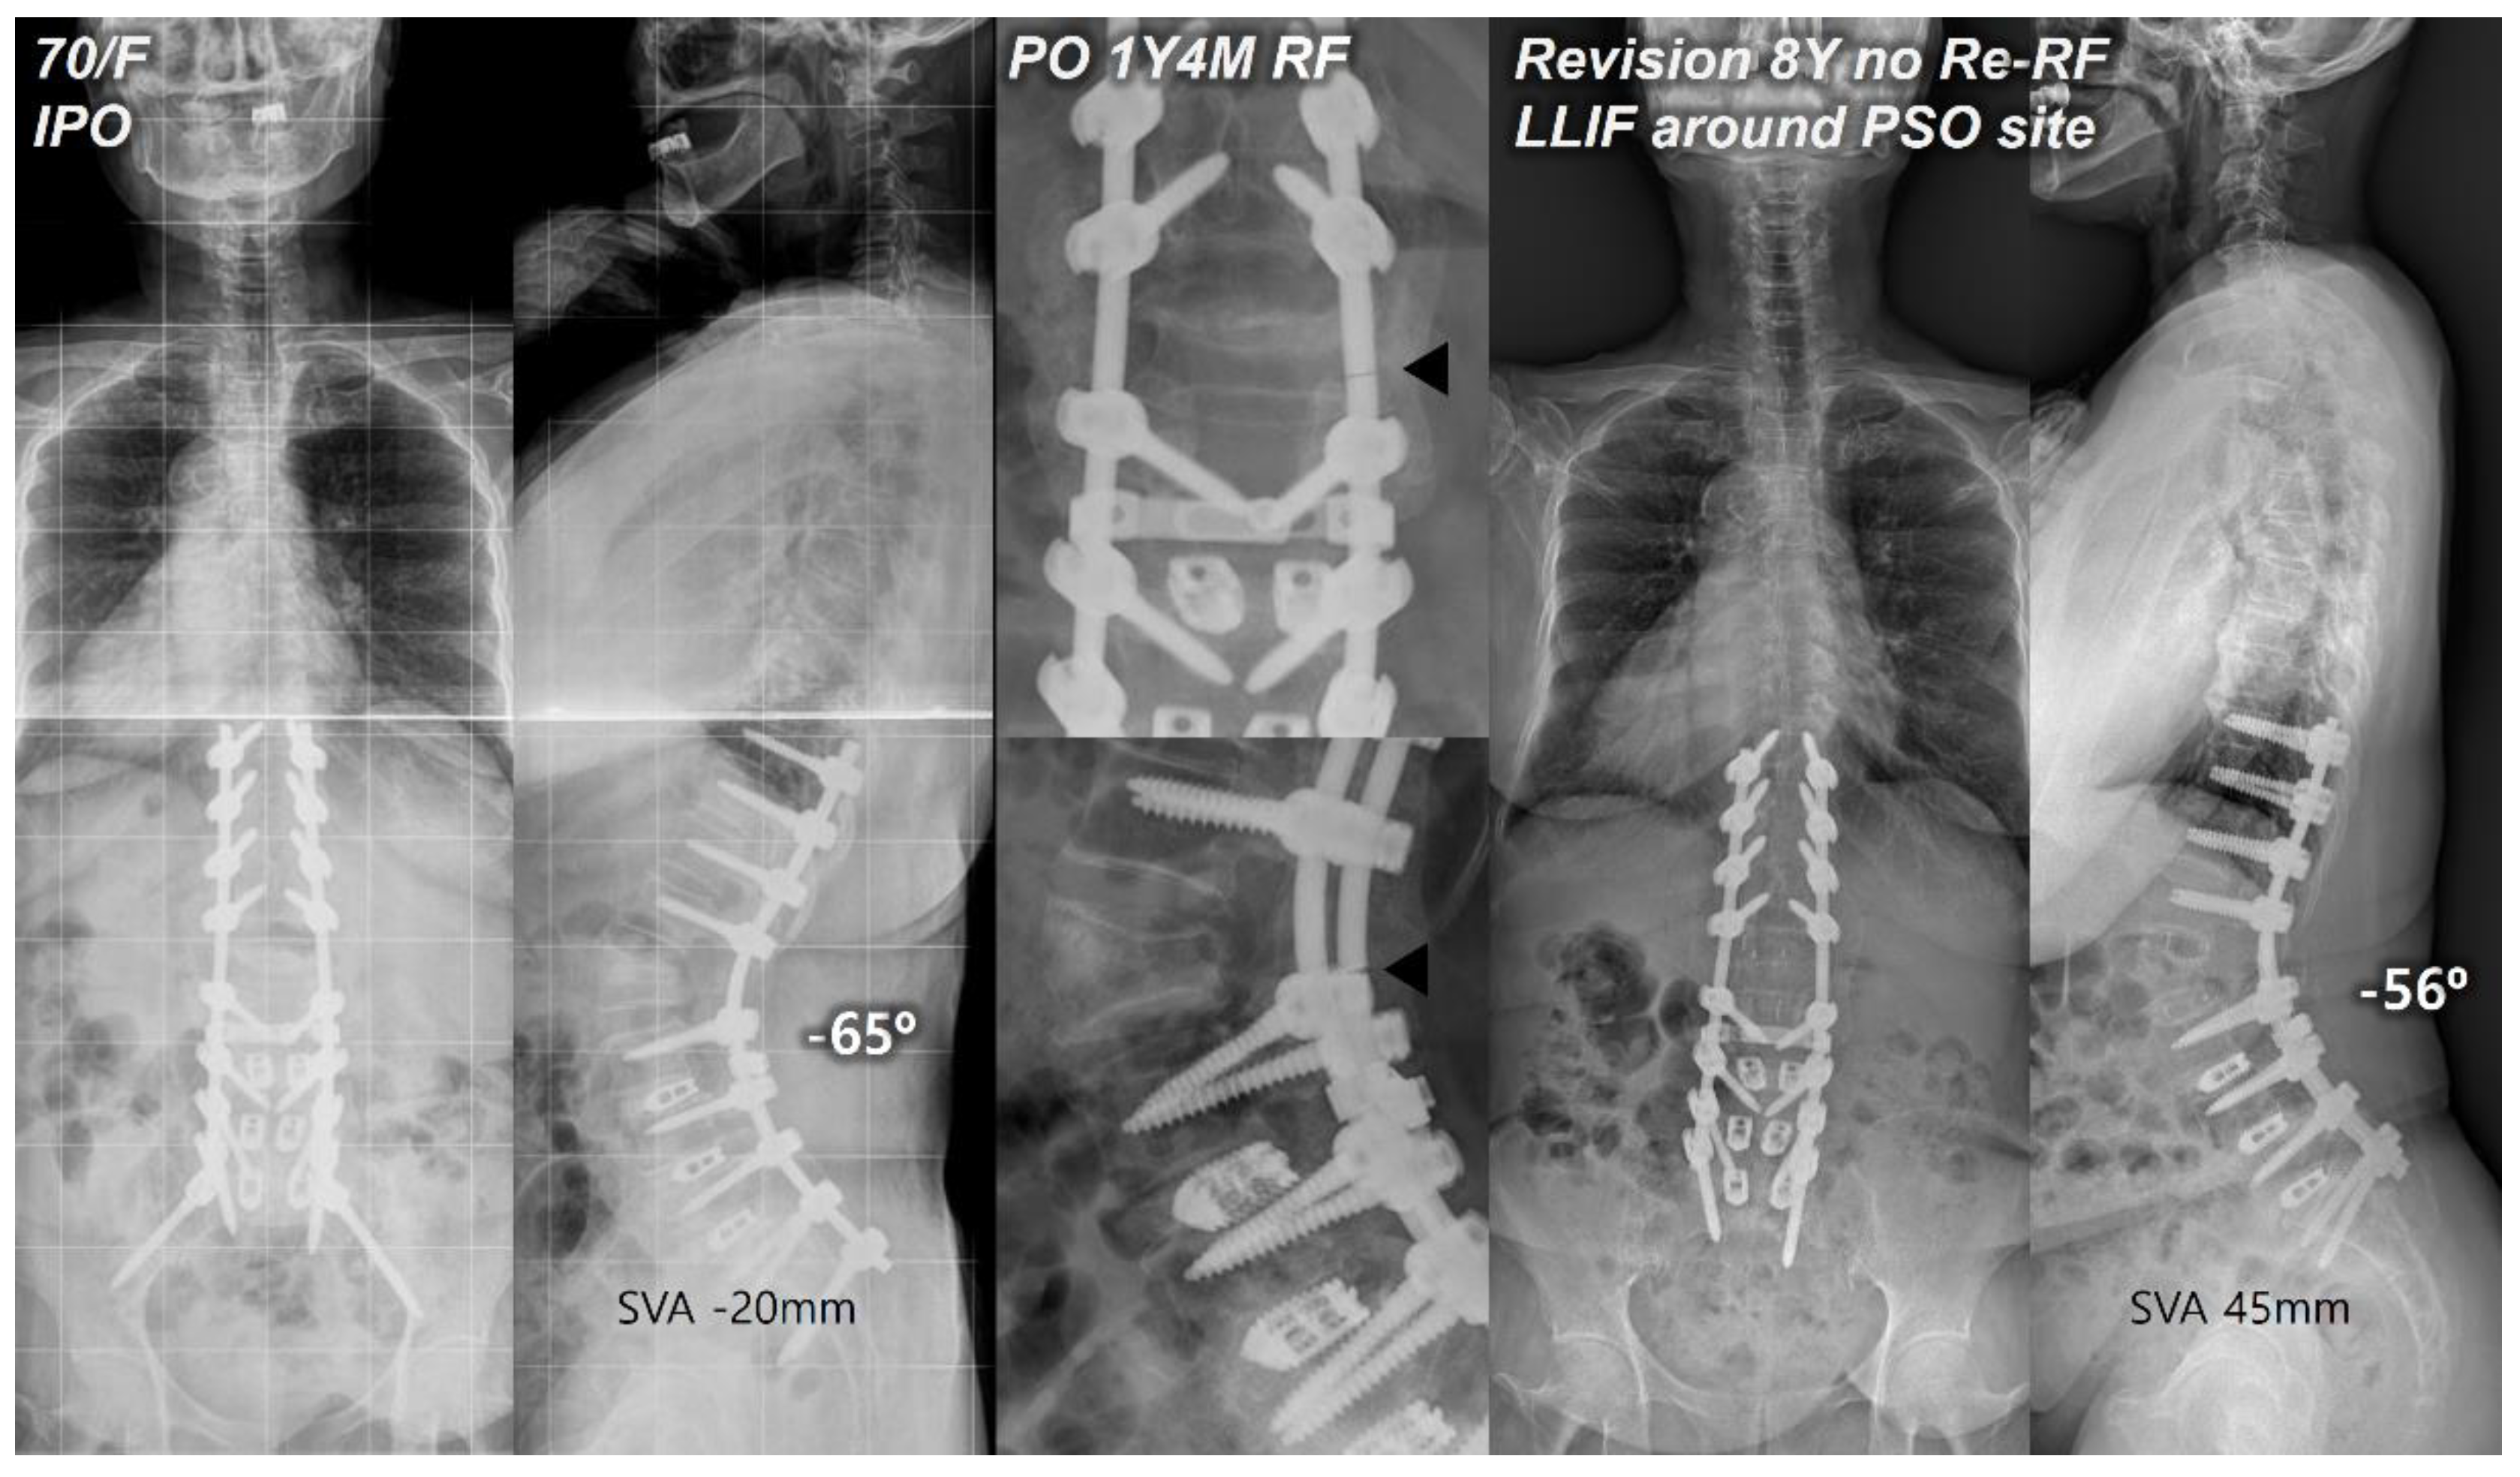

Figure 3. Postoperative standing radiographs of a 70-year-old female patient after T10-S1 posterior instrumentation with PSO on L2, and PLIF on L3-S1 with an optimal sagittal balance (SVA, -20 mm; TK, 12°; LL, -65°; PI, 57°; PT, 17°; SS, 40°). At 1 year and 4 months after primary deformity correction, RF (right rod) occurred at L2-3. At 8 years following revision surgery with bilateral rod replacement and LLIF around the PSO site, sagittal alignment was well-maintained without re-RF. Black triangles indicate the site of RF.

Bilateral Rod Replacement with LLIF around the PSO Site

None of the patients in the LLIF group had experienced re-RF (Figure 3). This result can be attributed to the reduced residual sagittal motion of the construct, the increased stress distribution through anterior support, and the enhanced stability via interbody fusion immediately above and below the PSO site [25]. This finding was consistent with that of a cadaveric study by Deviren et al. [26], which showed increased stability through placement of interbody cages above and below the PSO site in multiaxial bending conditions. Luca et al. [8] also reported that the management of revision surgery after PSO may require an addition of anterior column support to maintain correction and reduce complications. In the same vein, Dickson et al. [27] recommended interbody fusion above and below the PSO site to help reduce the risk of further pseudarthrosis. Therefore, providing the anterior column support through interbody work around the PSO site by either lateral or anterior approach may be a promising method for revision due to RF. However, further comparative studies are needed to assess the effectiveness of LLIF technique with respect to the prevention of RF and postoperative complications.